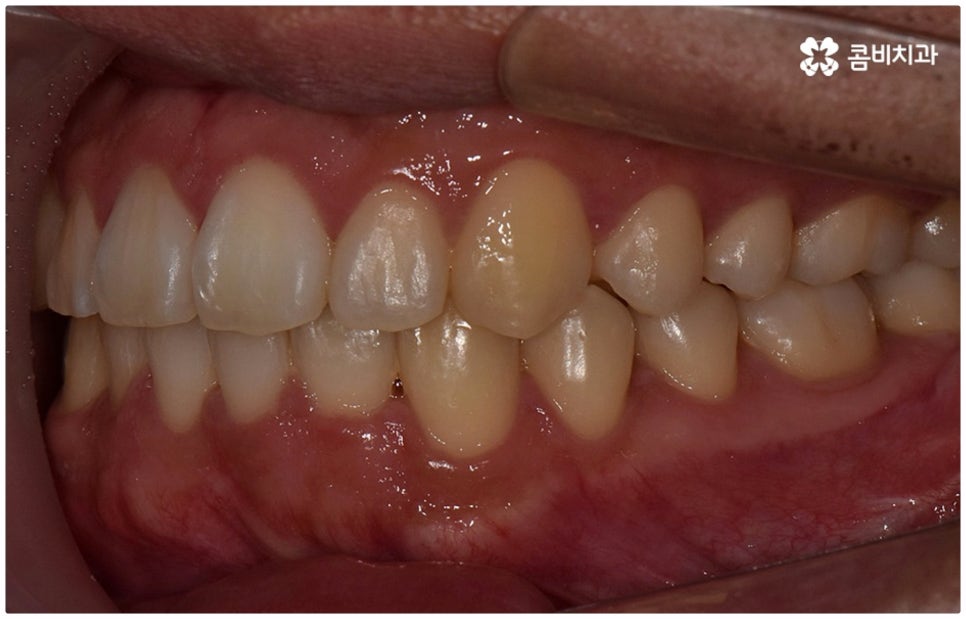

물론 교정 치료에 적기가 정해져 있는 것은 아니기 때문에 성인 이후 중장년 환자분들이라도 교정 치료가 불가능하지는 않으며 상황에 따라 비수술적인 방법으로도 얼마든지 불편함을 줄일 수 있는 경우가 있으니 정확하게 진단한 후 각자에게 맞는 교정 계획을 세워 무리하지 않게 치료를 진행하시길 바라고 있어요. 특히 턱관절과 관련된 부분을 개선하기 위해서는 양악 수술 밖에 방법이 없는 것이 아닌가 생각하셨던 분들이라면 먼저 치과에 내원하셔서 검진과 상담부터 진행해 보시면 마음의 부담을 덜 수 있어 좋을 거예요. 부정교합 3급 치열 (절단교합과 일부 반대교합이 병행되어 있음) 을 가지고 있는 성인분도 교정 치료를 통해 훨씬 자연스럽게 개선이 가능할 수 있으며, 관련 기술 개발 및 미니스크류 등 여러 장치의 발전을 통해 예전에는 적용이 어려웠던 케이스들도 이제는 교정 치료의 도움을 받을 수 있습니다.

위 사진은 이해를 돕기 위한 이미지이며, 환자의 동의하에 진행되었습니다.

전체 치료 기간은 약 18개월이 소요되었으며,

개인에 따라 출혈 및 부작용이 발생할 수 있고,

환자마다 치료 결과 및 기간이 상이할 수 있으므로,

정확한 치료 기간 및 치료 계획은

치과에서 상담을 받아보시길 권장 드립니다.